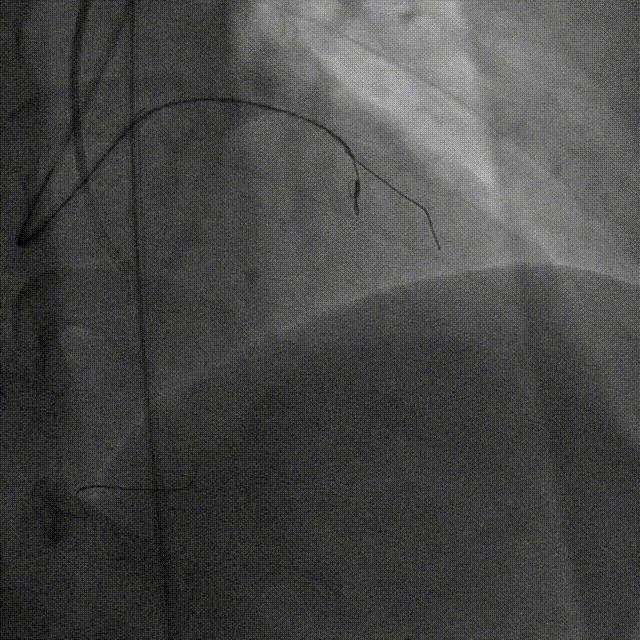

因侧枝血管严重迂曲,Caravel微导管无法通过侧枝,遂更换为1.5F HighTrack微导管顺利通过侧枝进入LAD远端

HighTrack微导管支撑逆向导丝前推至CTO病变体部,并跟进导丝进入CTO病变